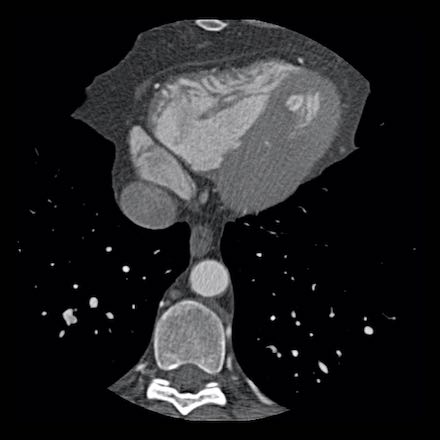

Continue with the next images of the same patient…

Same patient.

Double-oblique (A) and volume-rendered (B) images of the LAD showing the

location and the length of the plaque.

Also, the stenosis in the D2 branch of the LAD can be appreciated on the volume

rendered reconstruction.

Due to the degree of stenosis and the presence of napkin-ring sign (visible on

axial images) this patient underwent ICA where the presence of severe stenosis

was confirmed.